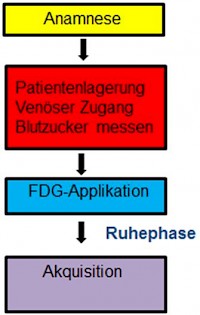

4. Welche Patientenvorbereitungen sind vor einer PET-CT mit 18-F-FDG zu beachten?

Mindestens eine 4-stündige Nahrungskarenz einhalten. Wasser oder ungesüßte Getränke sind erlaubt.

Mindestens eine 4-stündige Nahrungskarenz einhalten. Wasser oder ungesüßte Getränke sind erlaubt.- Eine genaue Anamnese erheben. Der Patient wird außerdem befragt ob ein Diabetes mellitus bekannt ist.

- Falls nach dem PET ein CT mit KM gefahren, Patientenvorbereitung vor KM-Gabe beachten.

- Der Patient auf eine bequeme Liege positionieren, ein venösen Zugang legen und Blutzucker (˂150 mg/dl) messen.

- Applikation von 300-400 MBq 18-F-FDG.

- Danach Lasix verbreichen zu Beschleunigung der Nierenausscheidung. Gegebenenfalls Buscopan verbreichen zur Ruhigstellung der Darmmuskulatur.

- Danach 60 min Ruhephase mit keiner Muskelaktivität, weil sich sonst das Radiopharmakon vermehrt in der Muskulatur anreichert.

- Vor Beginn der Aufnahme Entleerung der Blase.